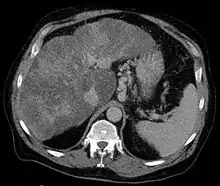

Gastric varices are dilated submucosal veins in the lining of the stomach, which can be a life-threatening cause of bleeding in the upper gastrointestinal tract. They are most commonly found in patients with portal hypertension, or elevated pressure in the portal vein system, which may be a complication of cirrhosis. Gastric varices may also be found in patients with thrombosis of the splenic vein, into which the short gastric veins which drain the fundus of the stomach flow. The latter may be a complication of acute pancreatitis, pancreatic cancer, or other abdominal tumours, as well as hepatitis C. Gastric varices and associated bleeding are a potential complication of schistosomiasis resulting from portal hypertension.

Patients with bleeding gastric varices can present with bloody vomiting (hematemesis), dark, tarry stools (melena), or rectal bleeding. The bleeding may be brisk, and patients may soon develop shock. Treatment of gastric varices can include injection of the varices with cyanoacrylate glue, or a radiological procedure to decrease the pressure in the portal vein, termed transjugular intrahepatic portosystemic shunt or TIPS. Treatment with intravenous octreotide is also useful to shunt blood flow away from the stomach's circulation. More aggressive treatment including splenectomy (or surgical removal of the spleen) or liver transplantation may be required in some cases.